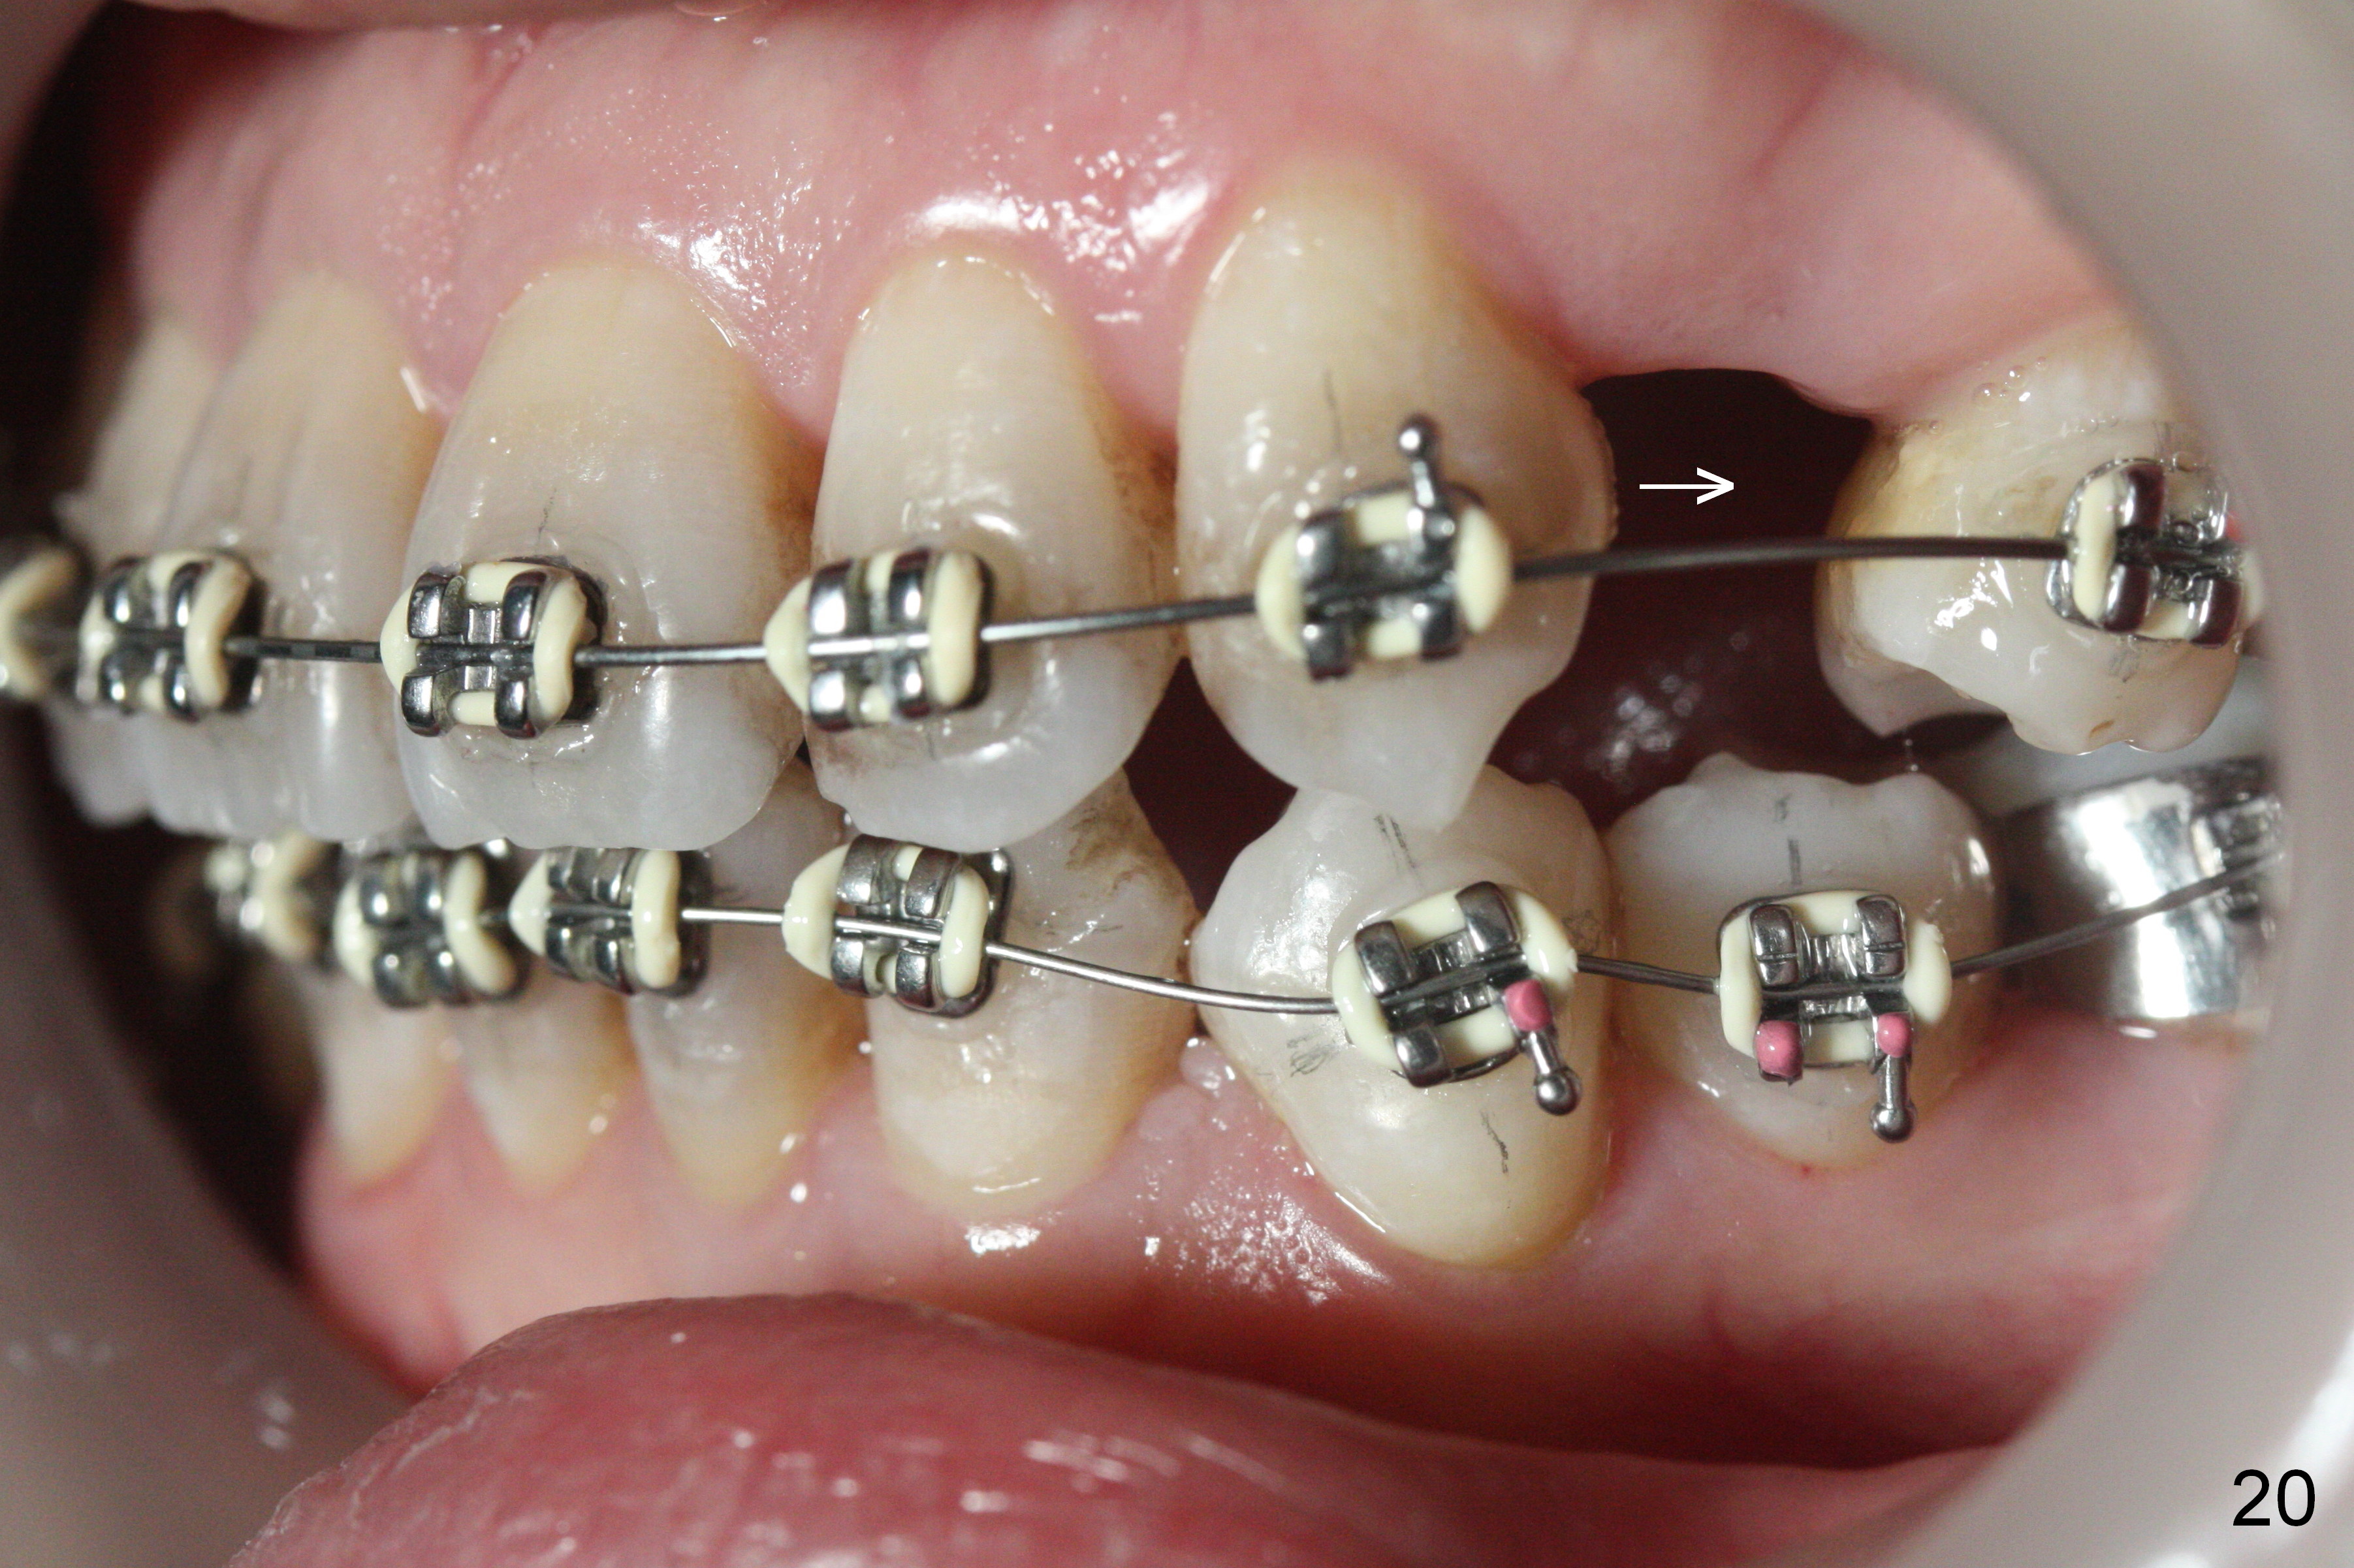

Fig.15-17 are taken nearly 2 months post banding. The upper 16 niti is still not fully engaged. Two weeks later, lower brackets are placed with 12 niti wire and occlusal composite (Fig.18-20). Overjet is excessive (Fig.19). Consider distalizing the upper anterior teeth when the upper arch wire changes to a rectangular one.

The rotation of the upper canines is not corrected much in the next 3.5 months (Fig.21, as compared to Fig.18). Distalization of the upper right canine is implemented by power chain, but this is not sufficient because of the anterior deep bite. Note the tension of 18 niti wire between LR 3 and 4 (^). Mini implants are going to be placed mesial or distal to L3s (Fig.22,23 circles) to intrude the lower anterior teeth with elastic or power chain (Fig.23 red line, 24 black area). The upper anteriors will have space to be distalized (Fig.24 arrow). If necessary, proximal reduction will be accomplished at LR3 (extra wide, Fig.25 black outline) for further overjet correction (arrows).